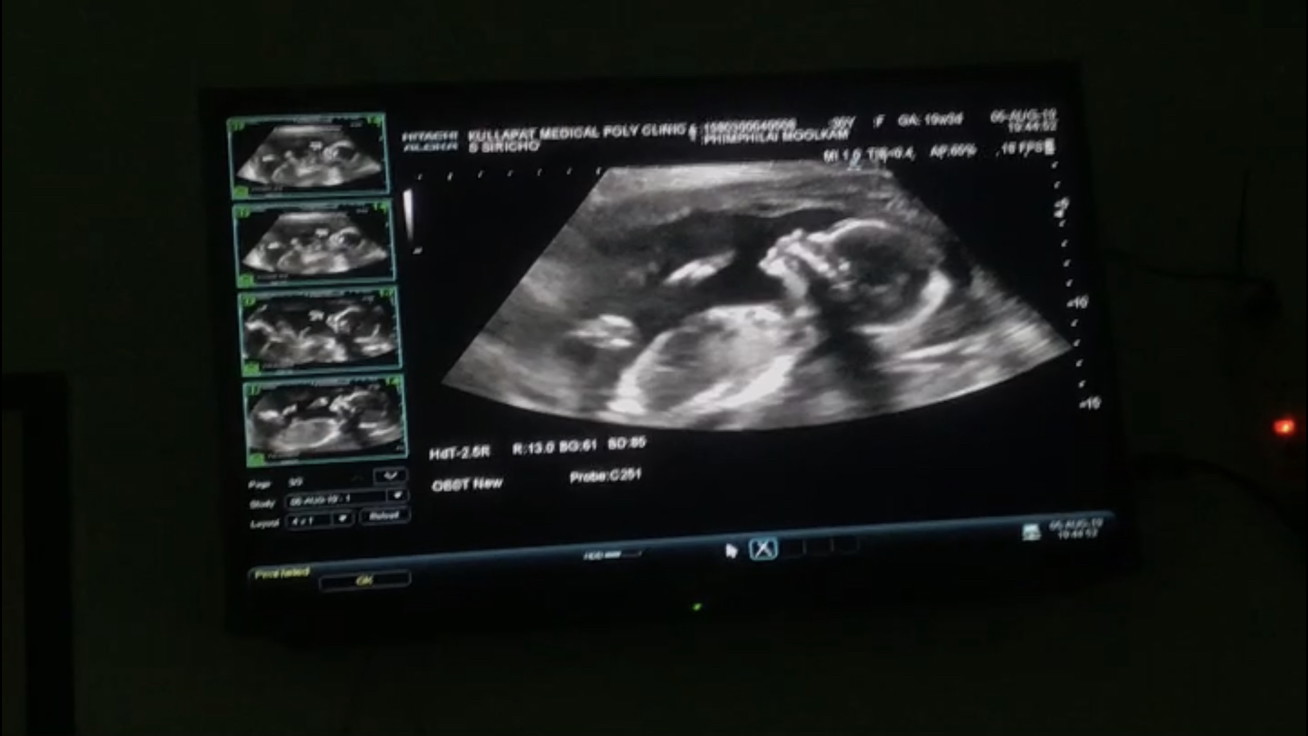

ซาว์ดทั้ง2รอบคุณหมอบอกได้ลูกสาวค่ะ. แม่แอบดีใจมากๆ. คลอดเดือนธันวาคม. แม่ๆบ้านไหนกำหนดคลอดเดือนธันวาบ้างค่ะ ได้ลูกเพศอะไรกัน